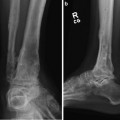

Fig. 2

(a–e) Pre-operative reformatted CT images reveal the rotational deformity that has developed between the hindfoot and forefoot at the tarsal-metatarsal junction